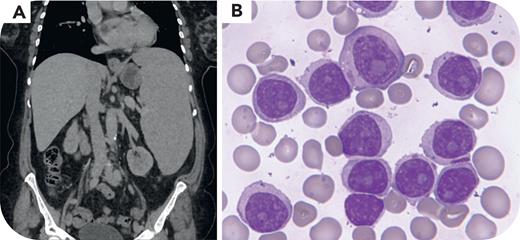

A 64-year-old woman was diagnosed with splenic marginal zone lymphoma following evaluation of lymphocytosis (lymphocytes, 4.6 × 109/L). At diagnosis, a computed tomography scan showed a 15-cm spleen but no lymphadenopathy. Twenty-four months later, she first complained of fatigue, left upper quadrant discomfort, and B symptoms (profuse evening sweating and a weight loss of 5 kg). Physical examination revealed a massive splenomegaly, measuring 23 × 18.7 × 9.1 cm on total body computed tomography scan (panel A, coronal view). A complete blood count revealed marked lymphocytosis of 284.13 × 109/L, severe anemia, and thrombocytopenia. Blood film showed 87% prolymphocytes of intermediate size, with a mature appearance and prominent nucleolus, some with pink cytoplasmic inclusions (panel B: May-Grünwald-Giemsa stain, original magnification ×1000). Flow cytometry confirmed a clonal B-cell population, CD19+, CD5+weak, CD10−, CD20+, CD22+, CD79b+, CD11c+weak, CD103−, similar to the findings at diagnosis. Molecular testing detected a TP53 mutation associated with deletion of the other allele, both absent at diagnosis. These findings are consistent with a prolymphocytic progression of her lymphoma. Treatment with rituximab and bendamustine was not effective. A partial response to zanabrutinib is ongoing at 9 months after progression.

Prolymphocytic progression is a rare and aggressive evolution of splenic marginal zone lymphoma. It should be suspected in the presence of rapidly progressive lymphocytosis and massive splenomegaly. The diagnosis is confirmed by a peripheral blood smear that reveals more than 55% prolymphocytes.